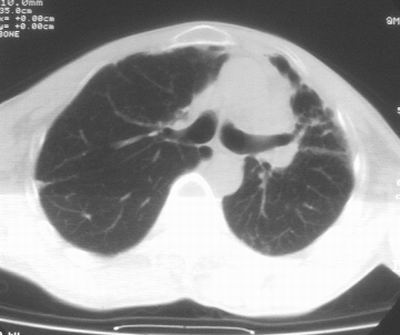

标题: CT11864:男,47岁,反复咳嗽、咯痰、咯血3年,请分析. [打印本页]

患者,男,47岁,反复咳嗽、咯痰、咯血3年,再发5天。痰培养未找到真菌、抗酸杆菌、癌细胞。

左肺上叶体积明显缩小,其内见多发透光区,纵隔向左侧移位,左肺下叶多发班片状病灶,边界模糊,1左肺上叶先天肺发育不全,2左肺下叶肺炎,

左肺上叶结核伴肺纤维化,纵隔移位,左肺下叶感染性病变,建议抗炎抗结核后复查,双肺气肿.

1)考虑为:左肺上叶肺结核(空洞形成),伴左下肺感染;不排除霉菌感染可能。2)肺气肿。

左肺上叶结核伴肺纤维化空洞形成并左肺下叶感染,纵隔牵拉移位,建议作进一步检查排除左侧肺霉菌感染可能。